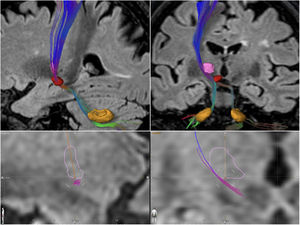

Pacientes y métodosTodos los pacientes incluidos en este estudio se sometieron al mismo procedimiento. La segmentación del Vim se realizó sobre secuencias volumétricas de resonancia magnética mediante el software Brainlab® (Boston Scientific, Natick, MA, EE. UU.). Se determinó la diana del tratamiento como la confluencia de 2planos en la superficie inferior del núcleo10, uno coronal oblicuo que pasa por el centro del núcleo y es paralelo a su eje mayor y otro sagital que pasa por el centro del núcleo (fig. 1), contralateral al hemicuerpo a tratar. El procedimiento se realizó en una resonancia magnética de 3 Tesla Signa Architect (General Electric Medical Systems. Waukesha, Wisconsin, Estados Unidos) y ExAblate 4000 MRgFUS (InSightec Inc., Haifa, Israel). Se observó el efecto clínico y la presencia de efectos adversos con una sonicación de verificación clínica (subterapéutica, idealmente entre 49° y 52°). En caso de que el efecto clínico fuese el deseado a juicio del neurólogo examinador, y libre de efectos adversos, se continuó llevando a cabo al menos 2sonicaciones terapéuticas en el mismo punto anatómico (≥ 55°, con límite en 60°)8 con monitorización clínica y de termografía por imagen continua. Se estableció como límite para el tratamiento un skull density ratio (SDR) ≥ 0,35, que se determinó en las semanas previas al tratamiento. Todos los pacientes se trataron con 30 mg de domperidona al día durante los 3días previos al procedimiento, con 8mg de ondansetrón una hora antes del procedimiento y 4mg adicionales antes del inicio de las sonicaciones.